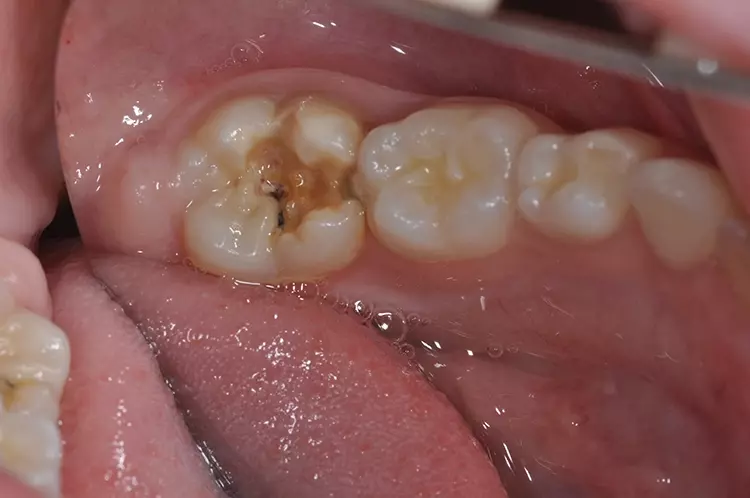

Typisch sind bei der leichten Form der Erkrankung weiße, cremige oder gelblich bis braune Opazitäten (Abb. 1). Im Gegensatz zur Dentalfluorose zeigt sich eine große Variabilität in Form, Farbe und Größe an den Zähnen innerhalb einer Mundhöhle. Bei der schweren Form bricht die Schmelzoberfläche nach dem Durchbruch des Zahnes im okklusalen Kontaktbereich aufgrund der Kaukräfte ein oder die Zähne weisen bereits im Durchbruch Defekte und Hypoplasien auf (Abb. 2).

Leider sind in diesen Fällen die Zähne häufig überempfindlich und neigen zu spontaner Schmerzreaktion auf äußere Reize wie Kälte oder bei Berührung (z.B. Zähneputzen). In diesen Fällen sollte auf ein Trockenpusten bei der Befundaufnahme verzichtet werden. Zudem muss damit gerechnet werden, dass die Lokalanästhesie schlechter wirkt [11,15].